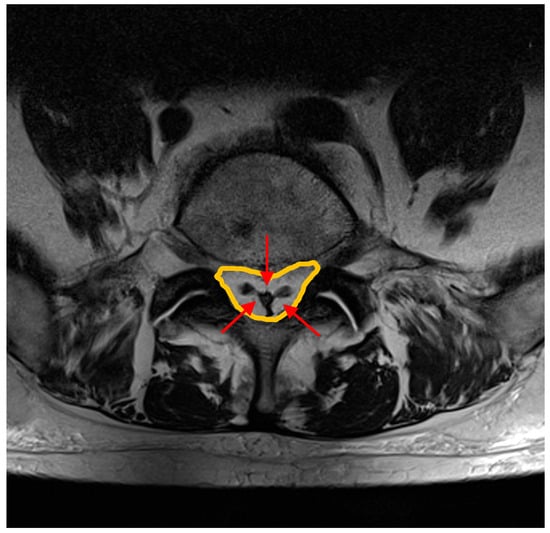

- Spinnato, P.; Lotrecchiano, L.; Ponti, F. “Y” sign in spinal epidural lipomatosis. Jt. Bone Spine 2021, 88, 105056. [Google Scholar] [CrossRef] [PubMed]